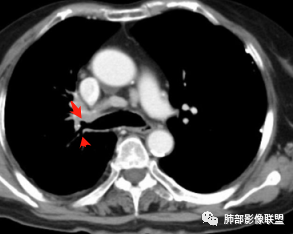

支气管影

前,后段都在,没有堵塞

支气管壁增厚,周围磨玻璃边界不清,提示炎症。胸膜下钙化符合结核

这个层面往上应该是尖段,显示不清

结核是肯定有。现在最大问题是尖段

近端显示不清,但是远端是粘液栓,可以认为是还行的

如果是近端鳞癌,远端应该会堵塞,不会整个肿块里面还有较为通畅的支气管

这个区域我们看到密度与周围一致,并不是肺癌伴周围不张的感觉,所以鳞癌暂时是不支持的

相应上叶尖端及前段支气管开口未能追踪(阻塞),开口处见钙化。病灶渐进性强化,并衬托出较完整尖段及前段含液支气管影。支气管开口区域未见异常高密度强化(如类癌等)及相对乏血供区(如鳞癌)。病灶区未见液化坏死。右上纵隔及胸廓入口区未见病灶胸膜外突破(栽赃)。